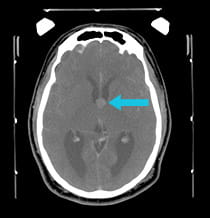

pre-surgical scan shows a colloid cyst of the third ventricle post-surgery scan showing completely removed colloid cyst

Pre-surgical scan shows a colloid cyst of the third ventricle.

A 41-year-old veteran of Operation Desert Storm had unremitting headaches, confusion, and fainting spells. MRI scans showed a large colloid cyst of the third ventricle.

The colloid cyst was completely removed using the minimally invasive Neuroendoport technique.

The patient's cognition and headaches improved immediately, and the fainting spells are gone. In the follow-up image, which was performed while the patient was still in the operating room, it is clear that the colloid cyst has been completely removed. Intra-operative imaging with a CT scanner allows UPMC neurosurgeons to confirm safe lesion resection prior to leaving the operating room.